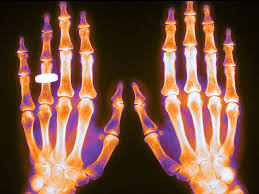

¿Existe potencial para el monitoreo de fármacos terapéuticos de agentes biológicos en la artritis reumatoide?

Br J Clin Pharmacol., 18 de enero de 2017 El uso de biológicos ha cambiado significativamente el manejo de la artritis reumatoide en la última década, convirtiéndose en el tratamiento de piedra angular para muchos pacientes. El arsenal terapéutico actual consiste en un poco menos de 10 agentes biológicos, con cuatro mecanismos de acción diferentes. Varios estudios han demostrado una gran variabilidad farmacocinética interindividual, lo que se traduce en la imprevisibilidad en la respuesta clínica entre los individuos.